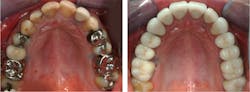

However, when blended with the clinical experiences of long-term CR clinicians, this information should be useful for you and your patients. The example in Figures 1 and 2 shows a patient who was not told by the practitioner that his previous restorations would eventually need to be replaced. This is the situation with many patients.